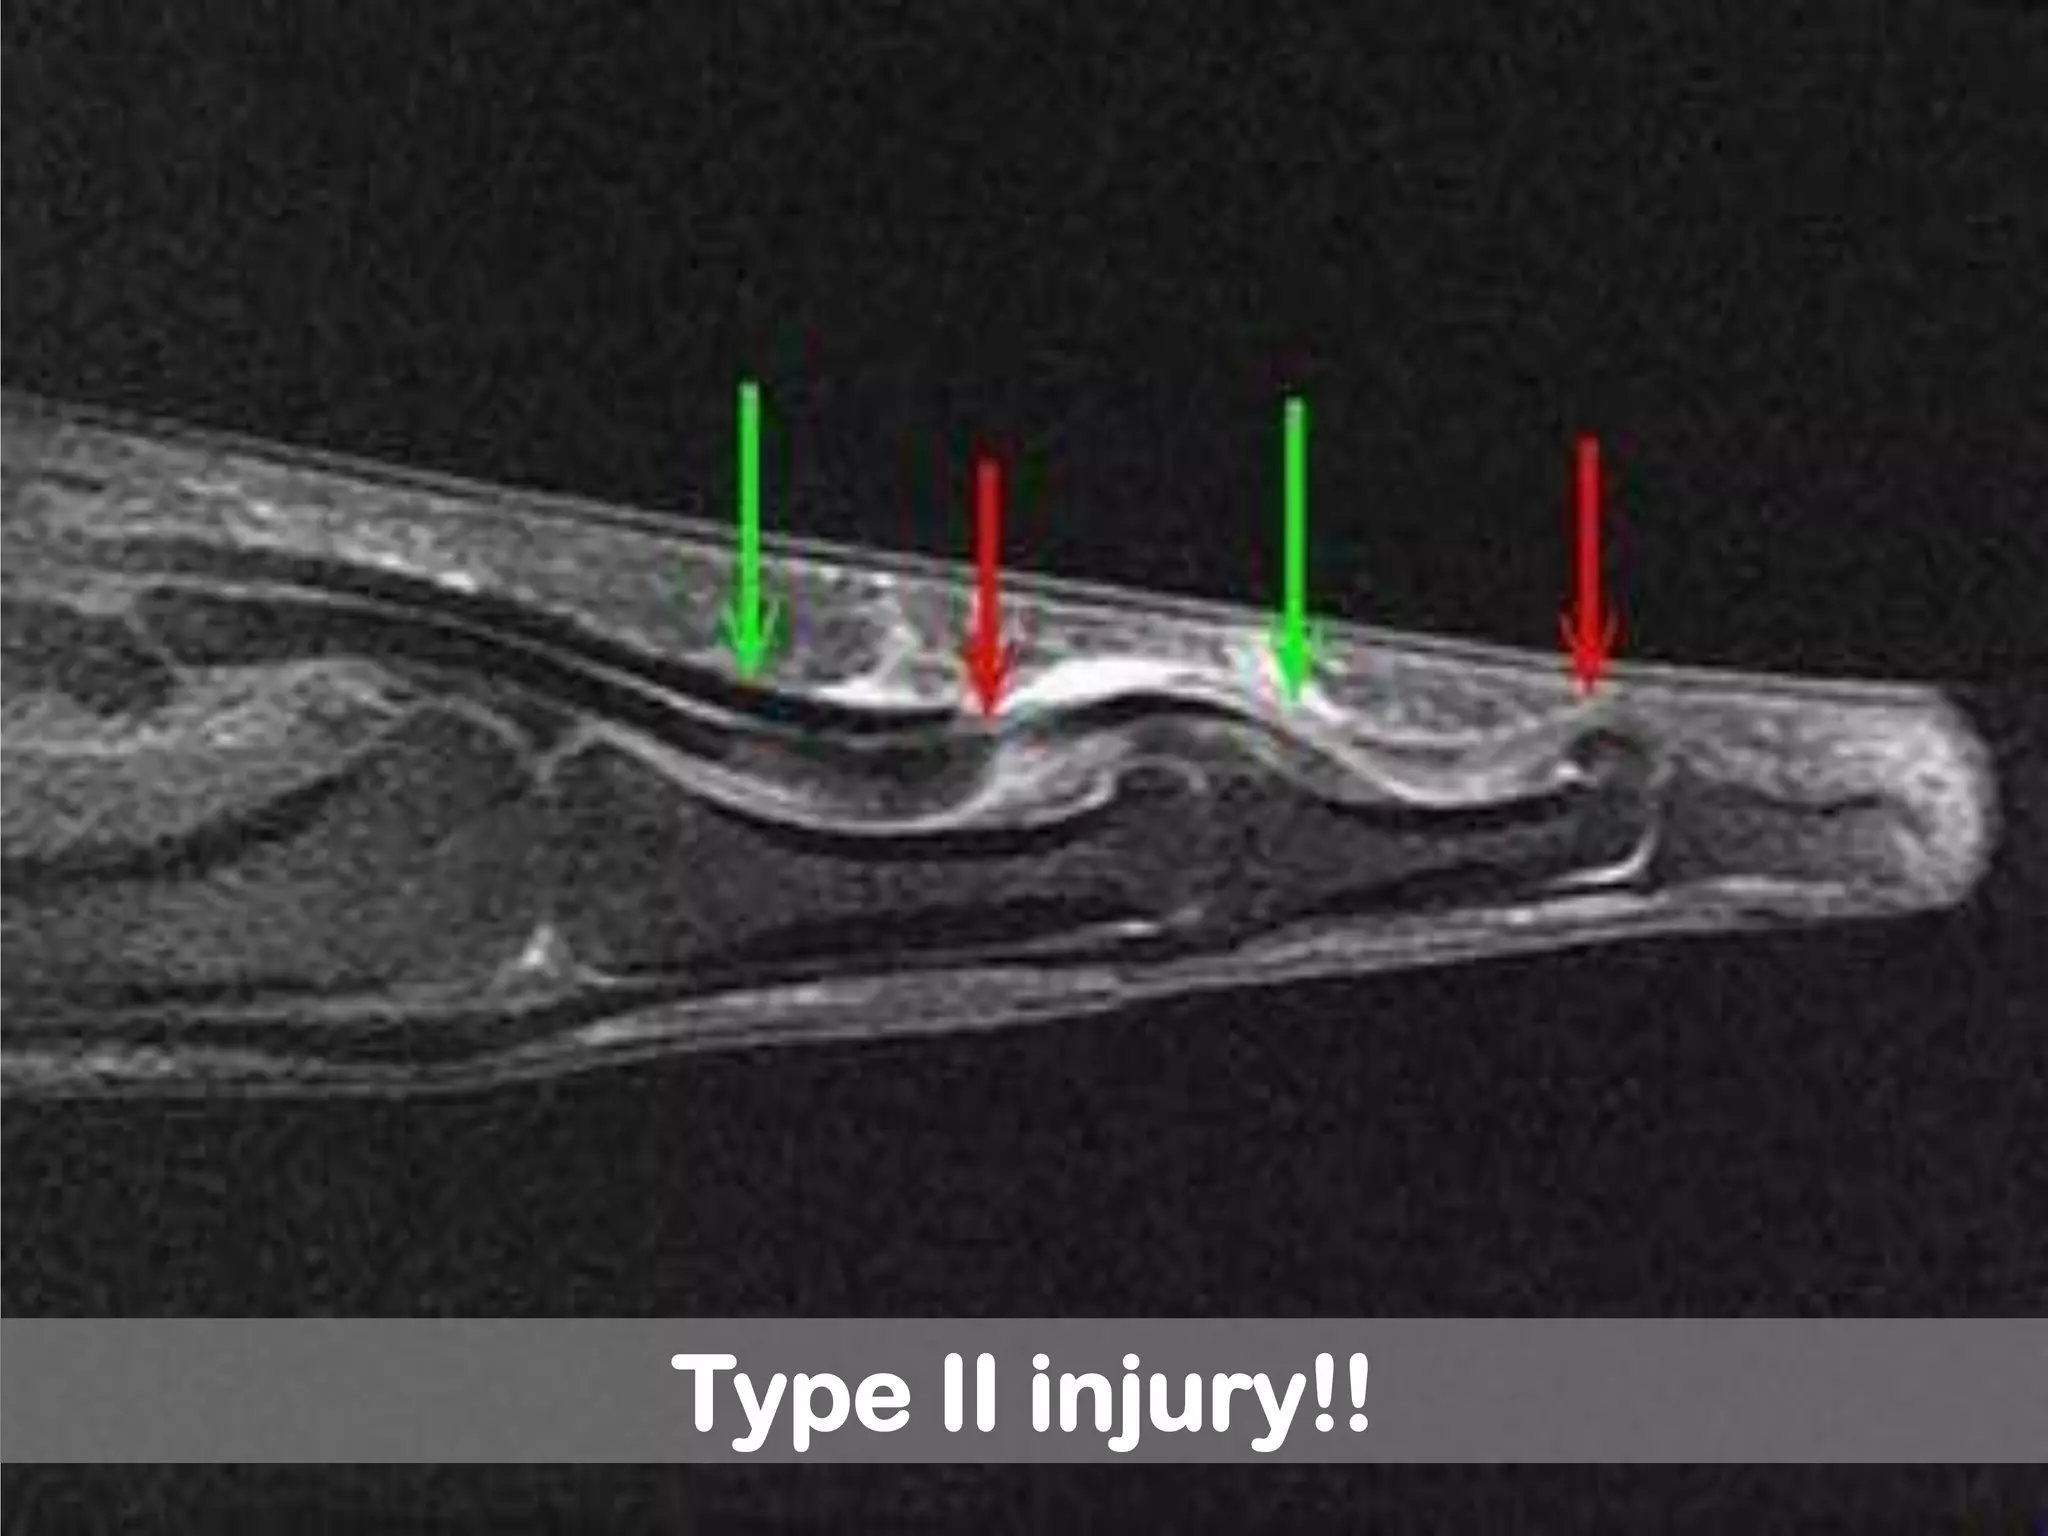

Leddy classification of zone I flexor

tendon injuries!!

Type II: tendon traped in the

sheath at PIP (unable to flex PIP)

Type II injury!!